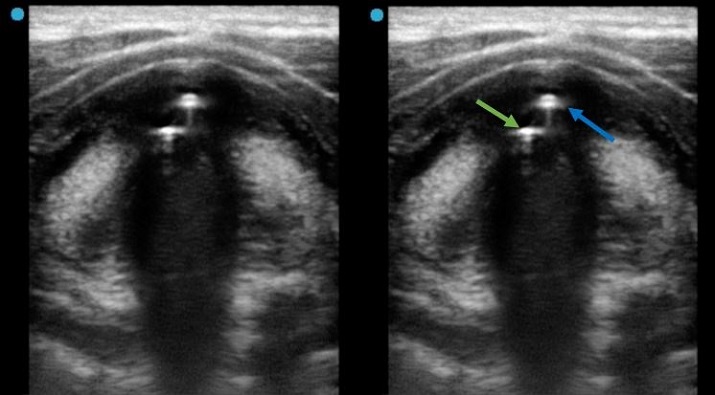

En la figura 6, con manguito vaciado, se observan dos artefactos de gas, el del tubo endotraqueal (flecha azul) y el del aire peritubo (flecha verde), que traducen la ausencia de un edema subglótico.

En el siguiente vídeo podemos apreciar el signo de la doble columna de gas que indica la ausencia de edema subglótico.